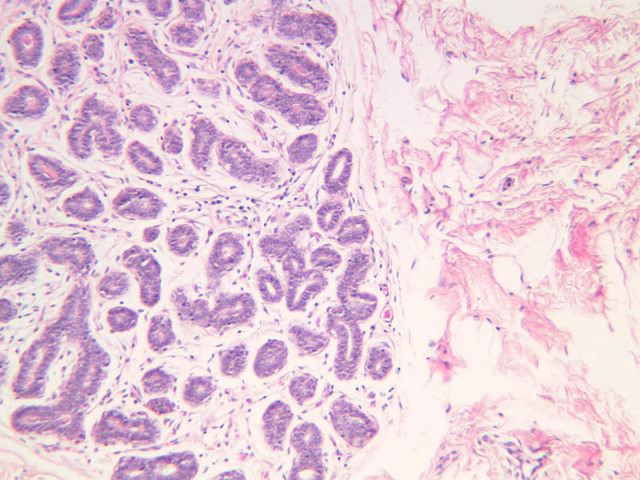

The endometrium of the cervical canal does not slough during the menstrual phase. The glands in this region are relatively large and extensively branched. They are lined by a tall simple columnar epithelium very active in the secretion of mucus. Occasionally these glands become blocked forming Nabothian cysts. The transition of the epithelium of the cervix to that of the vagina is abrupt and is in the region of the external os. At this point, the cervical simple columnar is replaced by the vaginal stratified squamous epithelium (slide B-98 [2.5x-labeled, 10x, 20x, 40x] [2.5x, 10x, 20x, 40x]). This is an area which is commonly inflamed as well as a primary location of cervical cancer.